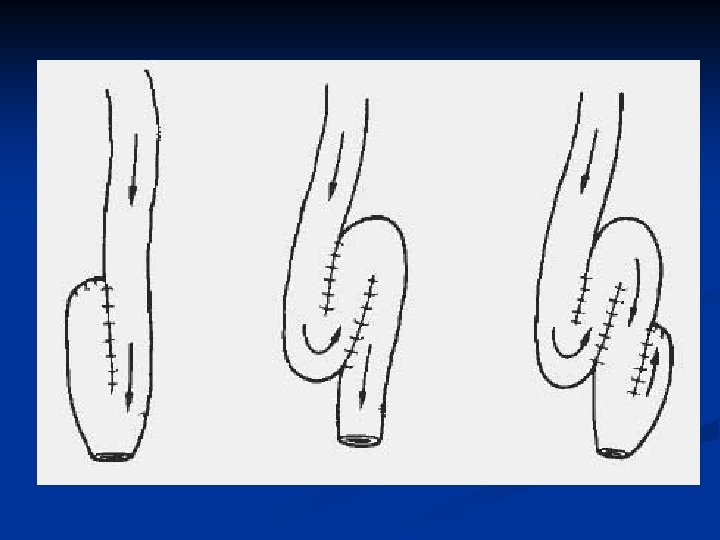

Familial adenomatous polyposis II. Treatment is surgical 1. colectomy + ileo-rectal anastomosis 2. total colectomy with permanent ileostomy ( cancer ) 3. „ restorative proctocolectomy“ - proctocolectomy with ileal pouch – anal anastomosis